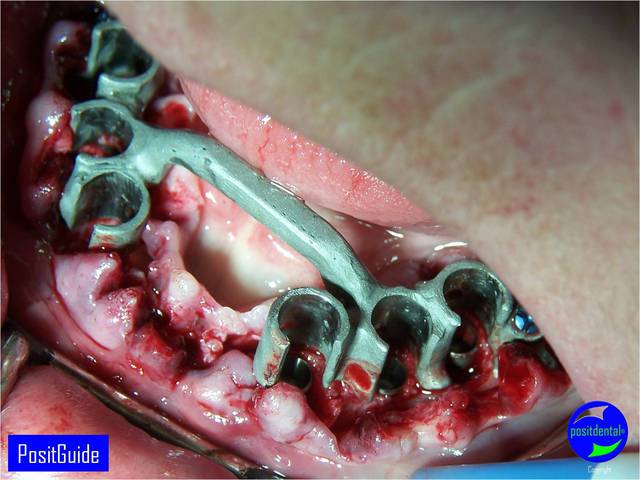

Mise en Charge Immédiate Post Extractionnelle , MCIPE partie chirurgicale de A à Z

implants in situ et S.I.A.O pré-opératoire